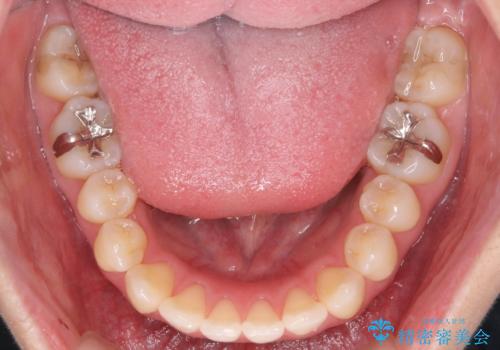

- 前歯の角度の改善を求めて矯正治療を希望し来院されました。

上下の歯は、上顎の歯が相対的に前に位置する咬合関係で押し出されるように前歯に角度がついている状態です。

矯正治療後、前歯のがたつき、咬合関係が改善され満足いただくことができました。